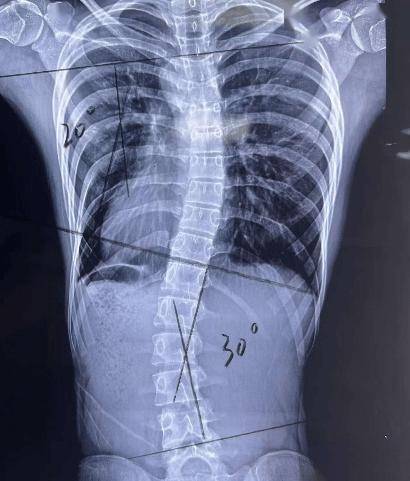

全脊柱X线影像学检查常用于AIS的筛查、手术及非手术治疗疗效的评估。通过确定侧弯段上下端,分别于上锥体上缘、下锥体下缘做平行线,并垂直于平行线做垂线形成夹角(Cobb角,如图3)。全脊柱X线下冠状面横向侧凸超过10°(Cobb>10°)是诊断侧弯的“金标准”。同时可评价髂骨骨骺发育情况,进行Risser评级,评估脊柱侧弯恶化风险。

对于Cobb角<20°的轻度侧弯,建议定期随访观察即可,一般建议3-6个月评估一次。观察过程中配合一系列物理治疗,主要包括跑、跳及游泳等体育锻炼、中医推拿,以达到增强脊柱周围肌肉的力量、改善脊柱的稳定性和平衡的目的。

适用于20°

对于脊柱侧弯Cobb角≥45°或保守治疗后进行性加重的患者,可通过手术治疗,改善患者外观、稳定躯干平衡、延缓脊柱弯曲进展,降低AIS短期或长期并发症发生率。